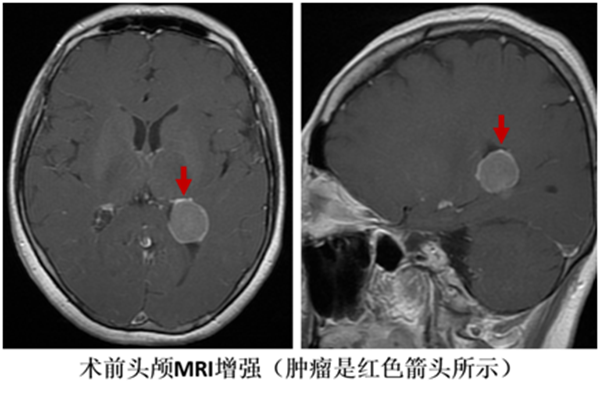

顱腦中的那枚腫瘤,是四年來一直困擾崔阿姨的心病。四年前,崔阿姨經(jīng)常沒來由的頭暈,體檢時做了頭顱磁共振,繼而發(fā)現(xiàn)了頭暈的“元兇”——側(cè)腦室三角區(qū)腦膜瘤。

對于有癥狀的腦膜瘤,以及瘤體較大、正在擴張、正在浸潤或伴周圍組織水腫的無癥狀腦膜瘤,醫(yī)生通常建議手術(shù)治療。但崔阿姨的腫瘤位置較深,且周圍有視輻射、語言中樞等重要的神經(jīng)功能區(qū),傳統(tǒng)手術(shù)方式可能會造成不同程度的視力或者語言功能障礙,聽到這些風險,崔阿姨對手術(shù)始終存有顧慮。

今年,崔阿姨隨訪檢查時,發(fā)現(xiàn)腫瘤有明顯增長趨勢,如果再不手術(shù),可能導(dǎo)致視力、語言障礙及肢體感覺運動障礙。她慕名找到我院神經(jīng)外科學科帶頭人謝正興主任,希望能夠找到安全性更高的手術(shù)方案。